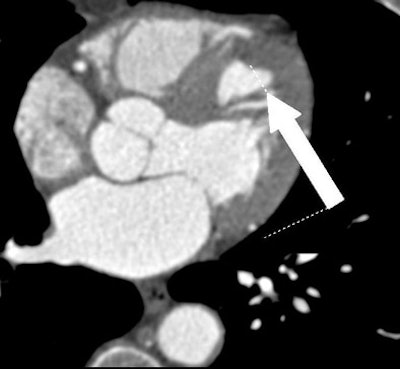

| All images were acquired in a 62-year-old man presenting to the hospital for evaluation of chest pain. Contrast-enhanced, retrospectively ECG-gated 64-slice-CT angiogram displays thrombotic occlusion of the mid left anterior descending (LAD) artery. |